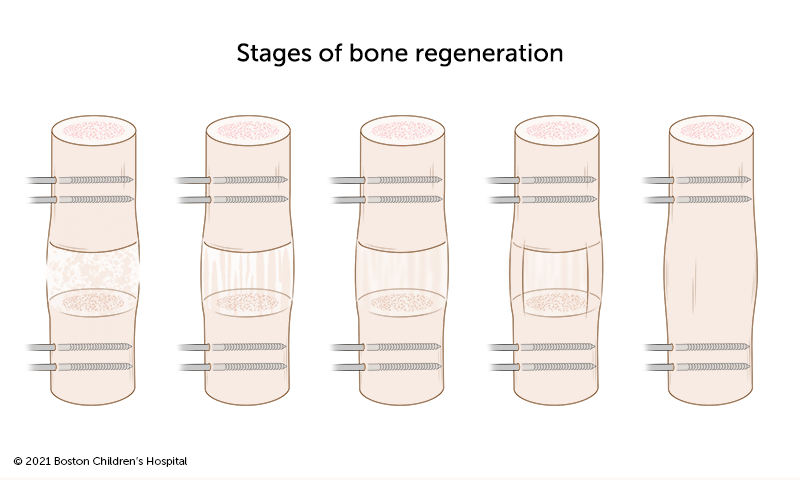

Limb-lengthening surgery stimulates new bone growth in the shorter leg or arm. Limb lengthening is performed only on patients with significant limb-length discrepancies that interfere with activities of daily life. It is typically performed when patients are in their late teens or early adulthood.

Lengthening surgeries take several months and may need to be repeated, depending on your child’s stage of growth and the extent of their limb-length difference.